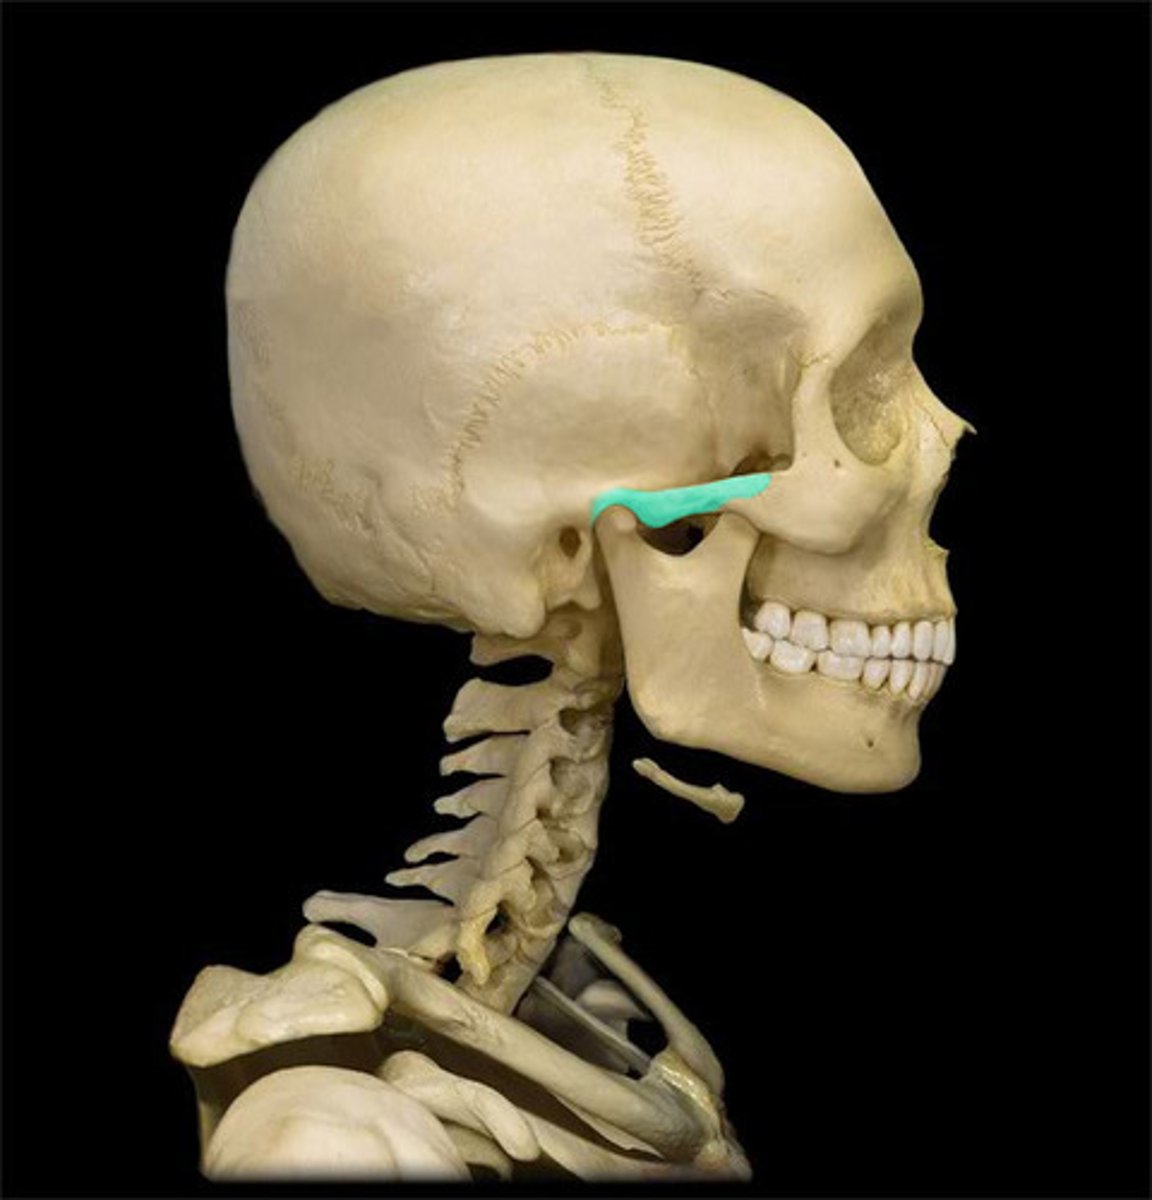

Zygomatic arch

Mandibular Fossa